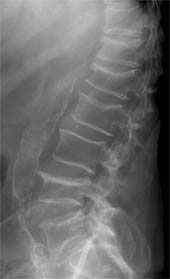

عکس بالا رادیوگرافی یک ستون مهره در فرد با پوکی استخوان را نشان می دهد.